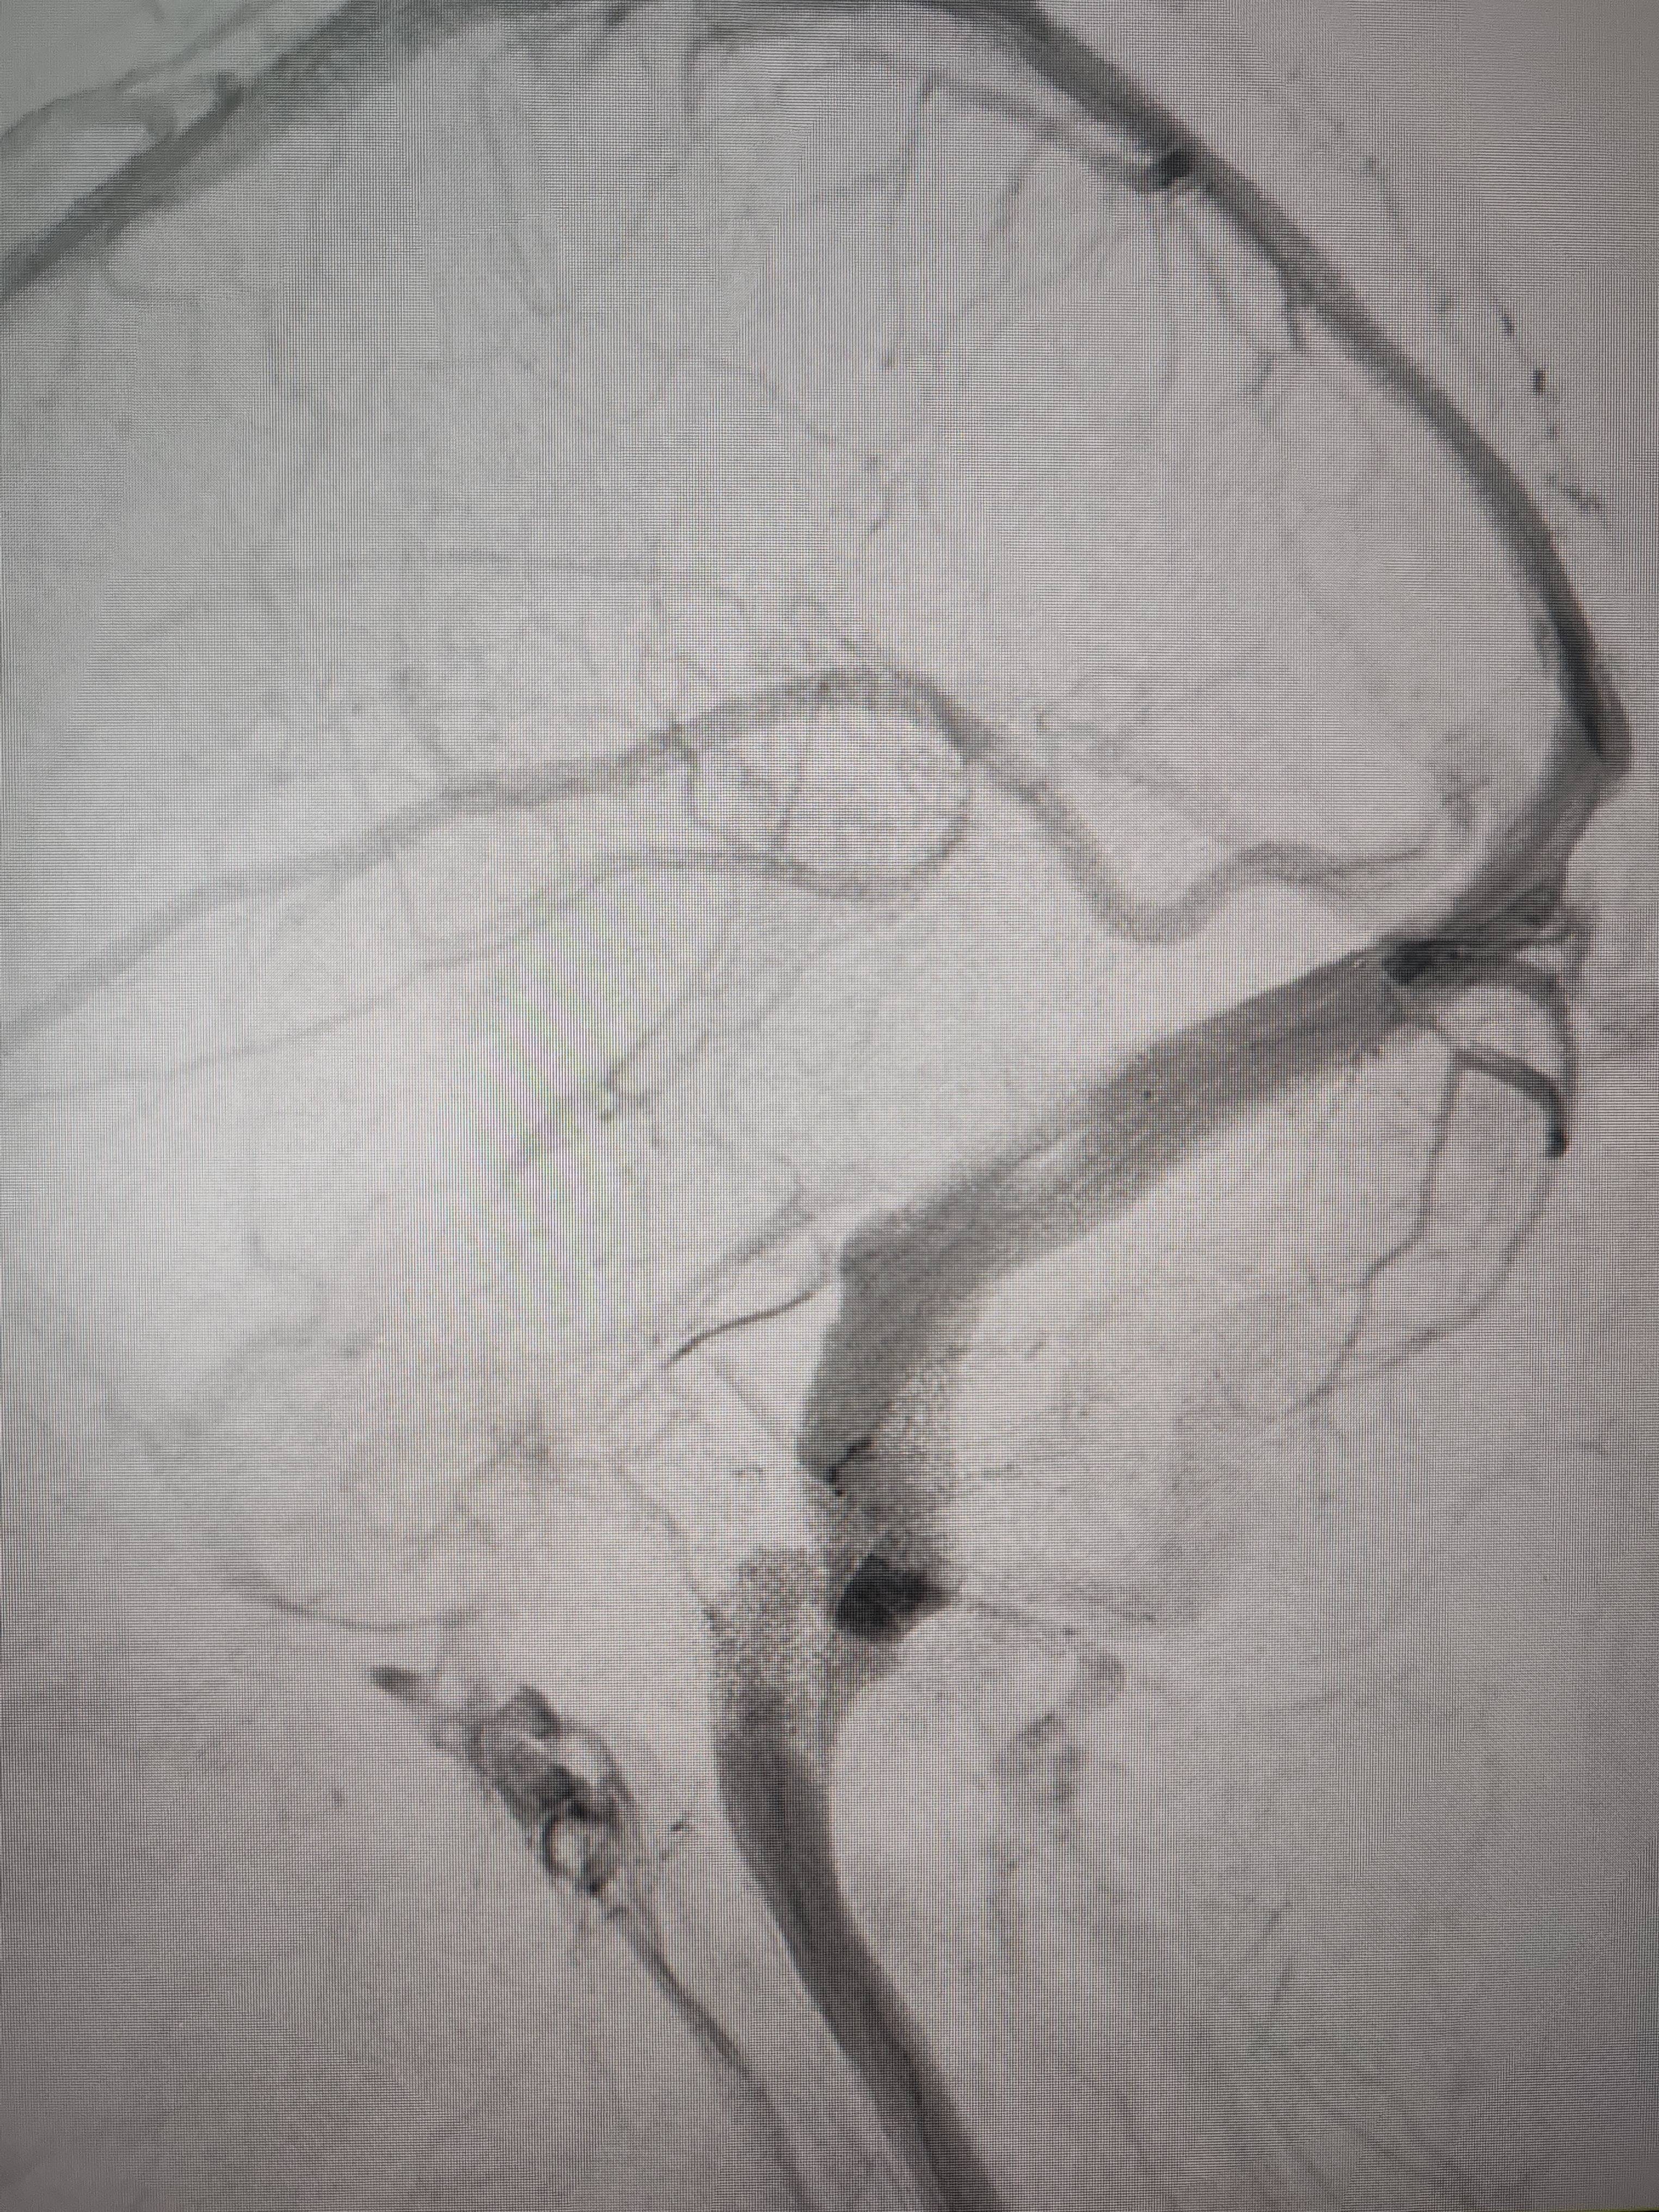

经过静脉窦支架置入手术治疗后,患者的静脉窦“堵点”被打通虚拟币小伙。 南方+ 欧阳少伟 拍摄

“从手术室出来,麻药清醒以后,我感觉整个世界都清静了,没想到效果这么立竿见影虚拟币小伙。”减轻病痛的赵女士,术后很是开心,次日就可下床自如活动,目前已康复出院。